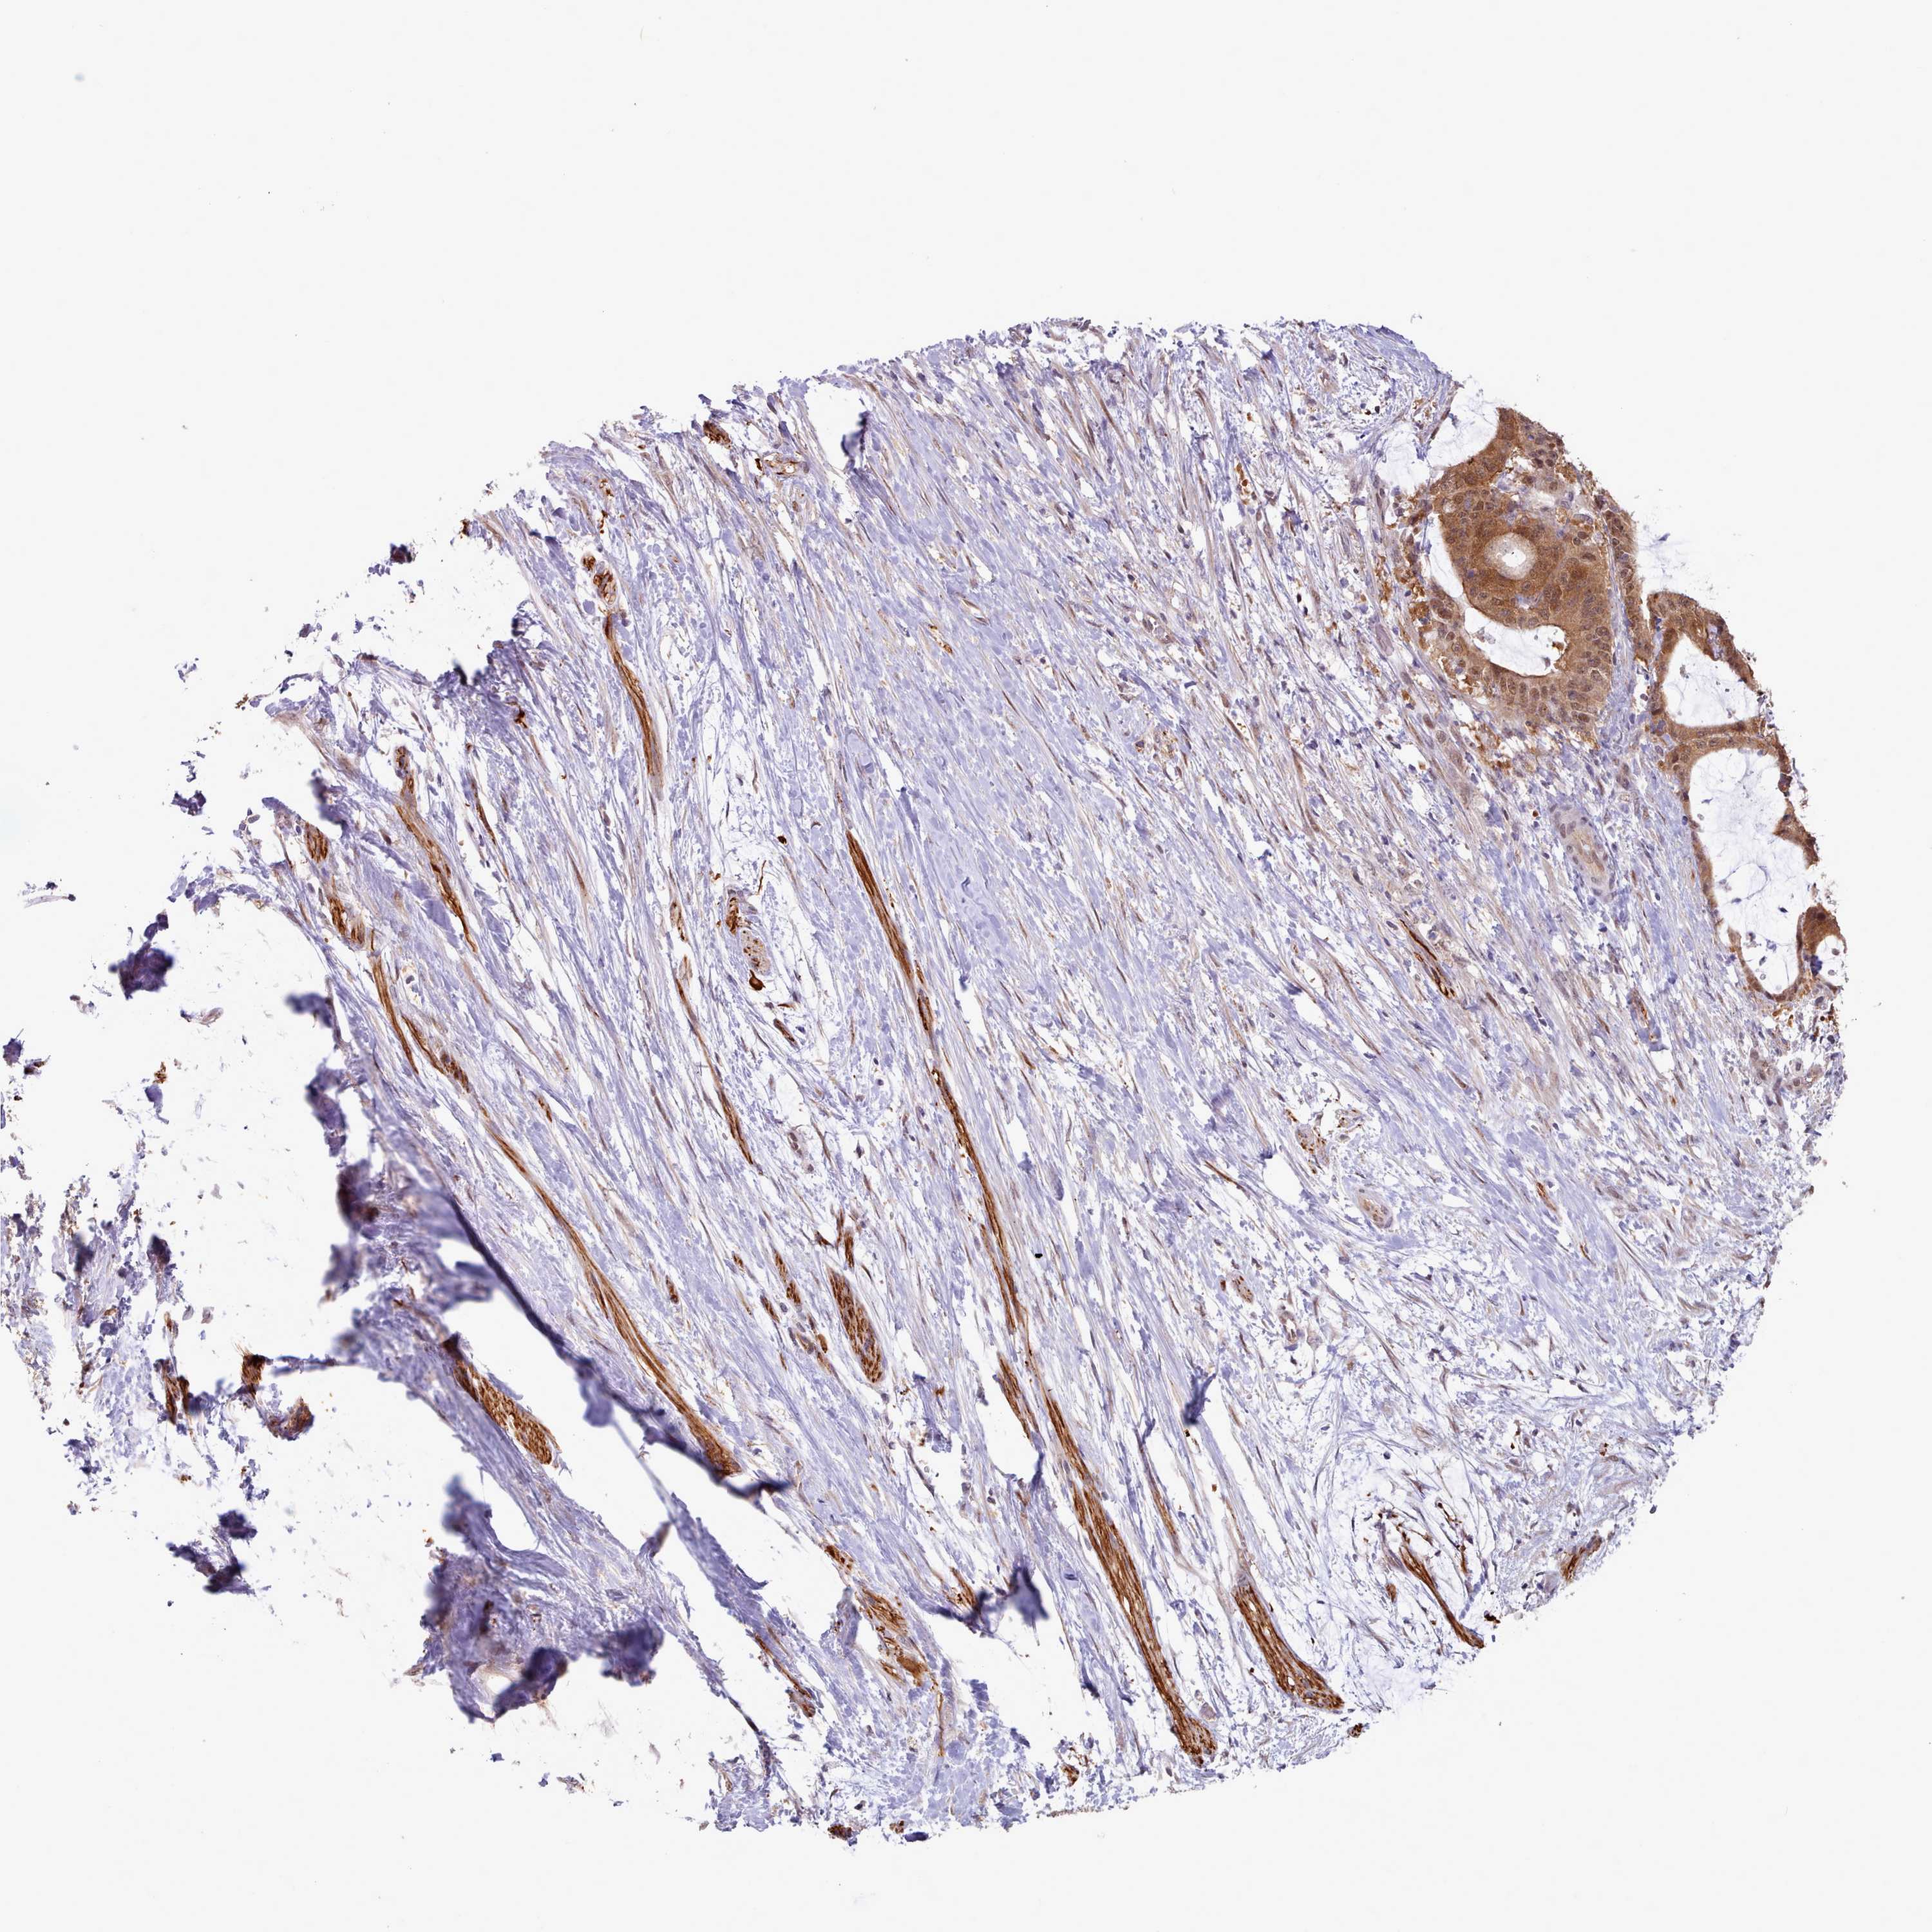

LIVER CANCER - Protein expressioni

A mouse-over function shows sample information and annotation data. Click on an image to view it in a full screen mode. Samples can be filtered based on level of antibody staining by selecting one or several of the following categories: high, medium, low and not detected. The assay and annotation is described here.

Note that samples used for immunohistochemistry by the Human Protein Atlas do not correspond to samples in the TCGA dataset.

Antibody stainingi

Antibody staining in the annotated cell types in the current human tissue is reported as not detected, low, medium, or high, based on conventional immunohistochemistry profiling in selected tissues. This score is based on the combination of the staining intensity and fraction of stained cells.

Each image is clickable and will lead to virtual microscopy that enables deeper exploration of all samples and also displays staining intensity scores, fraction scores and subcellular localization as well as patient and tissue information for each sample.

Antibody HPA041008

Antibody HPA041307

Staining

High

Medium

Low

Not detected

Intensity

Strong

Moderate

Weak

Negative

Quantity

>75%

75%-25%

<25%

None

Location

Nuclear

Cytoplasmic/membranous

Cytoplasmic/membranous,nuclear

Cholangiocarcinoma

Carcinoma, Hepatocellular, NOS